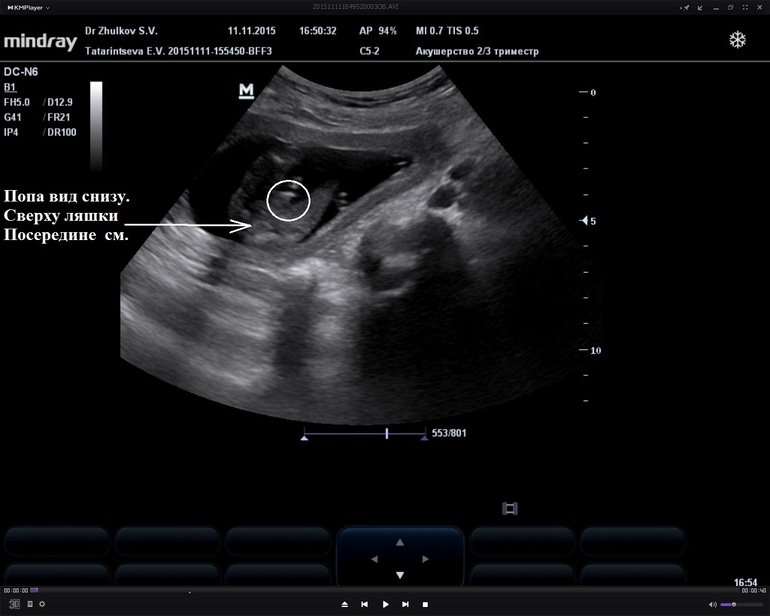

УЗИ в 17,5 недель. В 20 подтвердили мальчика. На заднем плане ещё пуповина